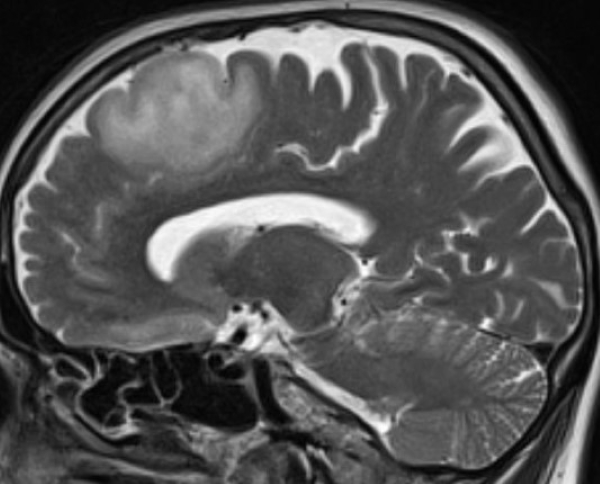

MRT Kopf – was sieht man?

Eine Kopf MRT liefert Ärzte und Radiologen detaillierte Bilder. Zu sehen sind das Gehirn, Schädelknochen, Blutgefäße und anderer umgebende Gewebe im Kopfbereich.

Hirntumor in der MRT